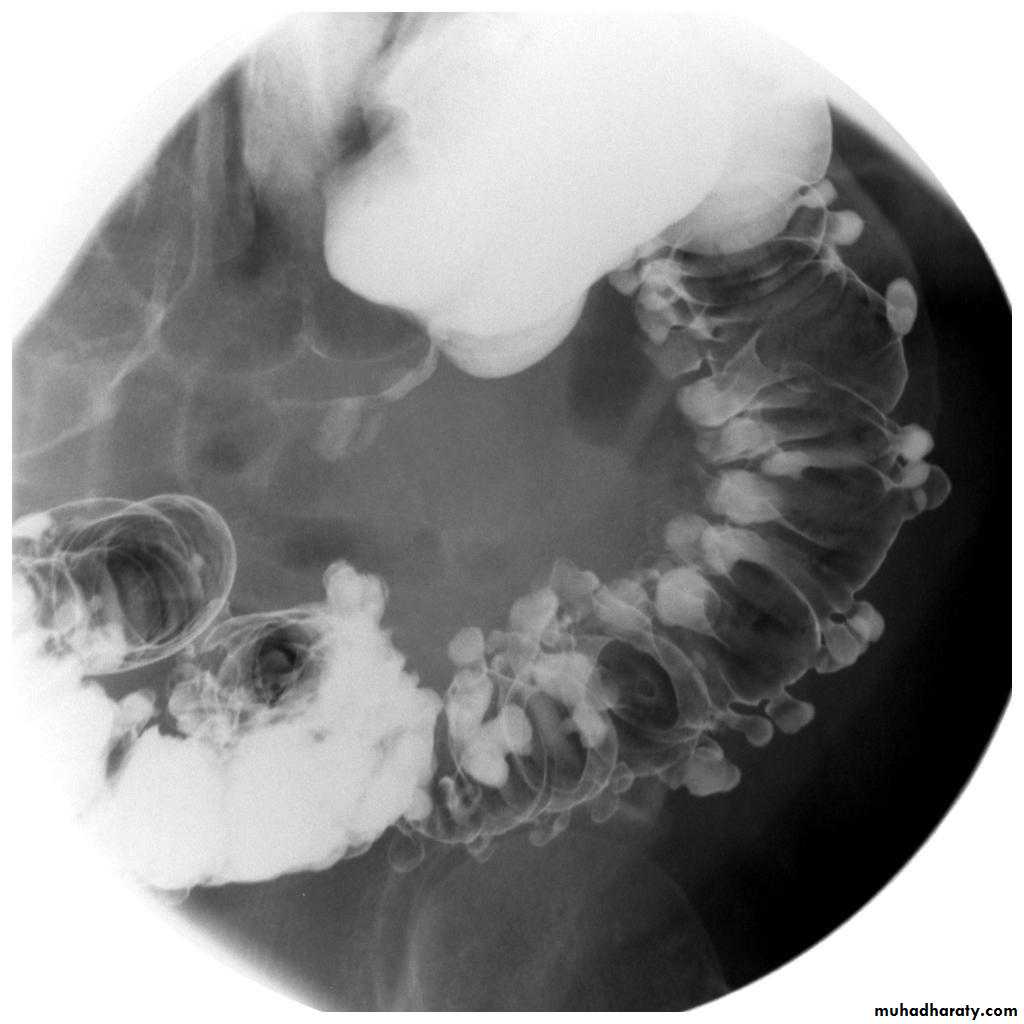

Diverticular disease

• Out-pouching of the mucosa through the muscular layer of the bowel wall

• Very common particularly in adults, commonest in the sigmoid.

• The diverticulae when filled with barium produce a spherical out-pouching with an narrowed neck (diverticulosis), some pouches do not fill with barium when inflamed (diverticulitis) causing symptoms such as sepsis, diarrhea or obstruction.

• The colon may show "saw tooth serrated" appearance from muscle hypertrophy.

• More extensive lesions produce perforation with fistulae into the bladder, small intestine or vagina, pericolic abscess and sometimes pneumoperitoneum.

• A stricture may occur in an area of recognizable diverticular disease otherwise cannot be differentiated from carcinoma.